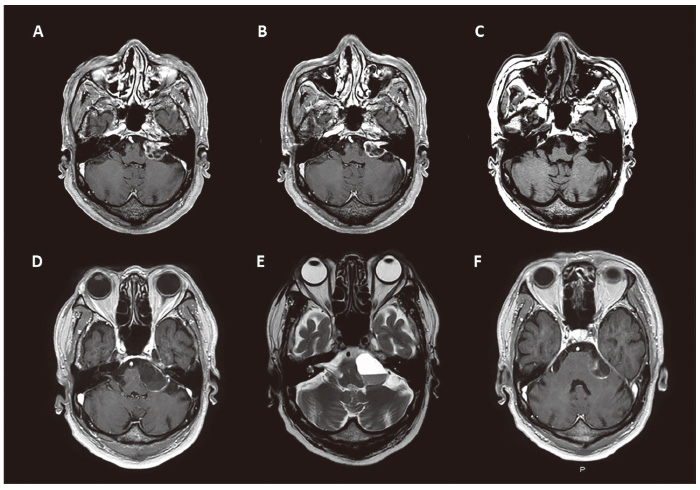

Follow-up MRI showed transient tumor volume expansion11 to 4.220 cc at 3 months post treatment (Fig. 1, Fig. 3A), followed by shrinkage to 2.220 cc at 6 months (Fig. 3B). By 5 years post-GKS, the tumor volume had remarkably decreased, with a maximum diameter of 8 mm and a volume of 0.295 cc (Fig. 3C).

However, 5 years and 7 months after treatment, the patient developed worsening left-sided hearing disturbance and ataxic gait. MRI revealed a 30 mm cystic lesion in the left CPA, causing brainstem compression (Fig. 3D-F). The patient also experienced left trigeminal neuropathy, left abducens neuropathy, left facial nerve palsy, severe gait instability, and inability to walk.

Fig. 3

Fig. 3 A: Follow-up image at 3 months after GKS showing transient expansion (tumor volume 4.220 cc). B: Tumor volume showed a decrease from the initial volume of 2.220 cc at 6 months after GKS. C: The tumor volume remarkably decreased to 0.295 cc at 5 years after GKS. D-F: 5 years and 7 months after treatment, the patient developed worsening left hearing loss and ataxic gait, and MRI revealed a large cystic lesion (tumor diameter, 30 mm) with an internal nodule in the left CPA, presenting compression of the brainstem. D, F: axial T1-weighted post-contrast MRI, E: axial T2-weighted MRI.